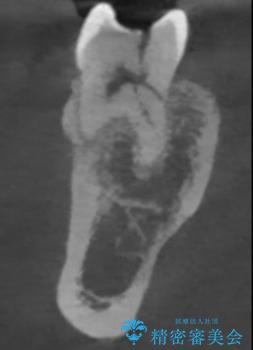

レントゲンやCTより、深くまで破折していることが分かり、抜歯が必要な状態でした。

歯槽骨の状態は良好であったため、抜歯即時埋入インプラントによる補綴治療を行うこととしました。